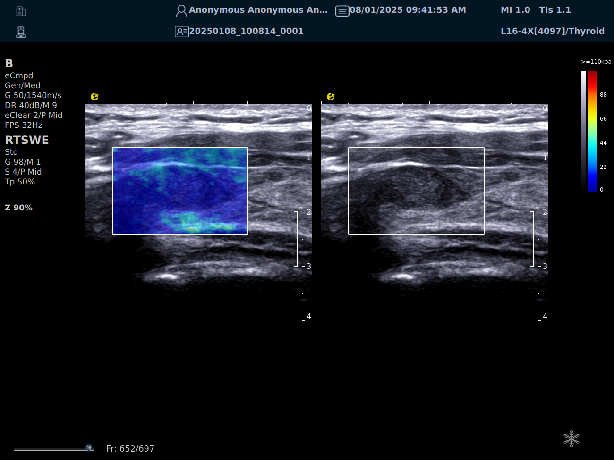

实时剪切波弹性成像

评估组织的软硬,并且提供定量数值,从而提示组织的良恶性。

image.png

鉴别诊断、精准分级、定量评价、穿刺引导、疗效评估、随访观察